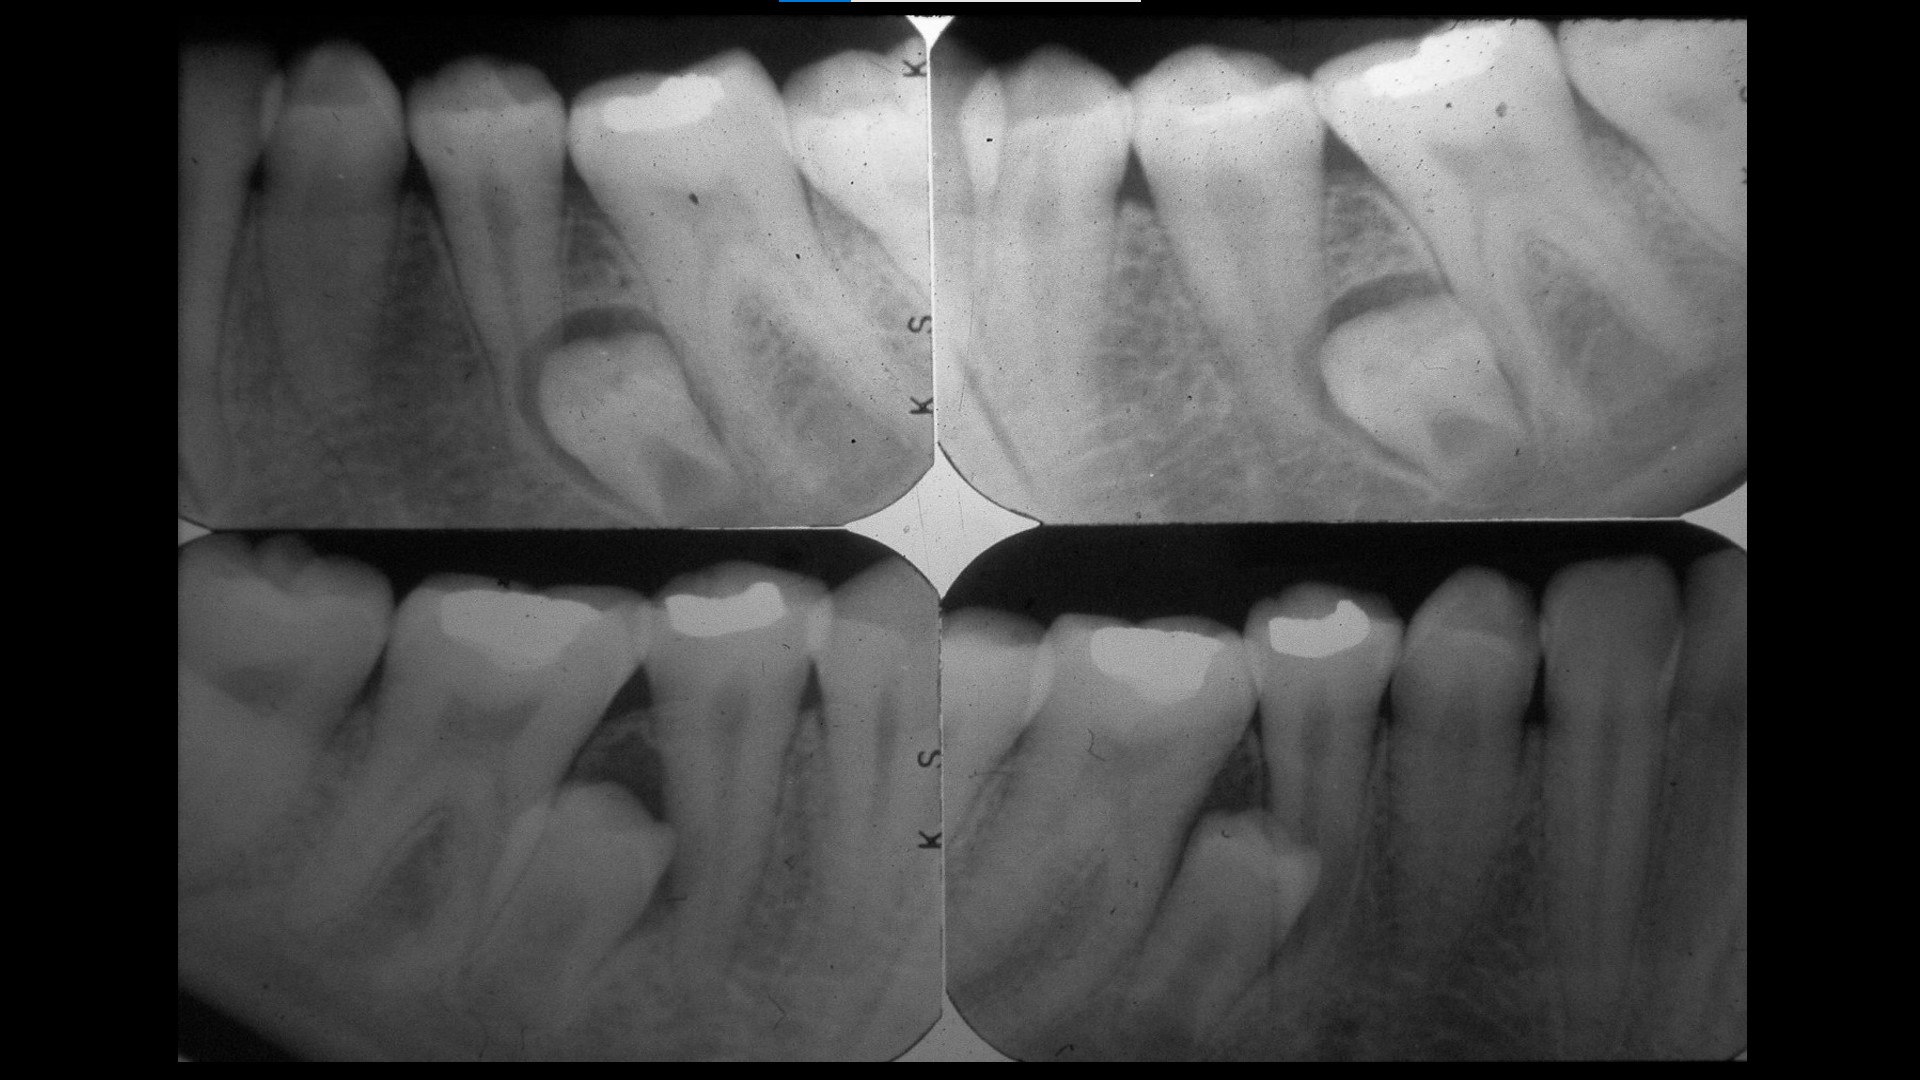

Impacted teeth

Oral Surgical Procedures